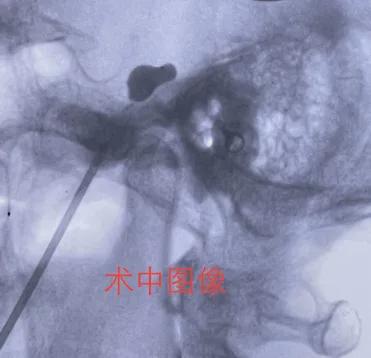

¡¡¡¡ÐìŮʿ£¨»¯Ãû£©75Ë꣬ÈýÄêǰ·´¸´ÓÒ²àÑÕÃæ²¿ÌÛÍ´£¬Õï¶ÏÊÇÈý²æÉñ¾­Í´¡£¸ßÁäÓöÉÏÈý²æÉñ¾­Í´£¬¿ÉνÊÇ¡°Óпà˵²»³ö¡±£¡»¼ÕßÌÛÍ´Ö÷Òª·Ö²¼ÓÚÓÒ²à¶î²¿ÉÏò¢ÇøÓò¡£½øÊ³£¬Ï´Á³£¬Ë¢ÑÀ¾ù¿ÉÓÕ·¢£¬Æð³õ¿Ú·þÒ©ÓÐЩЧ¹û£¬¿É½üÈý¸öÔÂÖ¢×´¼ÓÖØ£¬Ò©ÎïÖÎÁÆÒѾ­Ã»ÓÐЧ¹ûÁË£¬Ã¿Ìì¸Ð¾õ»è»è³Á³ÁµÄ²»Êæ·þ¡£ÔÚһλȬÓúµÄ²¡ÓÑÍÆ¼öÏ£¬ÐìŮʿÂú»³ÆÚ´ýµØÕÒµ½Á˹þÒ½´óËÄÔºÉñ¾­Íâ¿ÆÍõÑ©·åÖ÷ÈΣ¬¾­¹ýÏà¹Ø¼ì²éºÍÆÀ¹Àºó£¬¿¼ÂÇ»¼Õ߸ßÁ䣬²»ÊʺϿªµ¶ÊÖÊõ£¬Ó뻼Õß¹µÍ¨ºó¾ö¶¨ÊµÊ©Èý²æÉñ¾­°ëÔ½ÚÇòÄÒѹÆÈÊõ¡£ÊõÖо«×¼ÓÖÇáÈáµØ½«Ò»¸ù¶ÛͷϸÕë´©´Ìµ½Â­µ×µÄÂÑÔ²¿×£¬Í¨¹ý´©´ÌÕëÄÚÇ»½«Î¢ÇòÄÒµ¼¹ÜµÄÇòÄÒË͵½ÐÎ×´Ïñ°ë¸öÔÂÁÁÒ»ÑùµÄÈý²æÉñ¾­°ëÔÂÉñ¾­½ÚµÄÄÒÄÚ¡£ÀûÓõ¼¹Ü×¢Éä΢Á¿ÔìÓ°¼ÁÀ©ÕÅ΢ÇòÄÒ£¬±»À©ÕŵÄ΢ÇòÄÒÔÚX¹âÕÕÉäϳÊÏÖÀæÐΣ¬Ô¼Îª»¨ÉúÃ×´óС¡£Ñ¹ÆÈÁ½·Ö°ëÖÓ£¬ÊÖÊõ¼´Ë³Àû½áÊø¡£ÐìŮʿÕû¸öÊÖÊõÈ«¹ý³ÌÎÞÖª¾õ¡¢ÎÞÌÛÍ´¸Ð£¬È«ÂéÇåÐѺóÁ³²¿ÌÛÍ´Á¢¼´Ïûʧ£¬×¡Ôº¹Û²ì1Ììºó³öÔº¡£

±ØÍþ½¨Ôº20ÄêØ­Èý²æÉñ¾­Í´¡¢Ã漡¾·ÂεÈ­Éñ¾­¼²²¡ÈçºÎÖÎÁÆ(ͼ2)